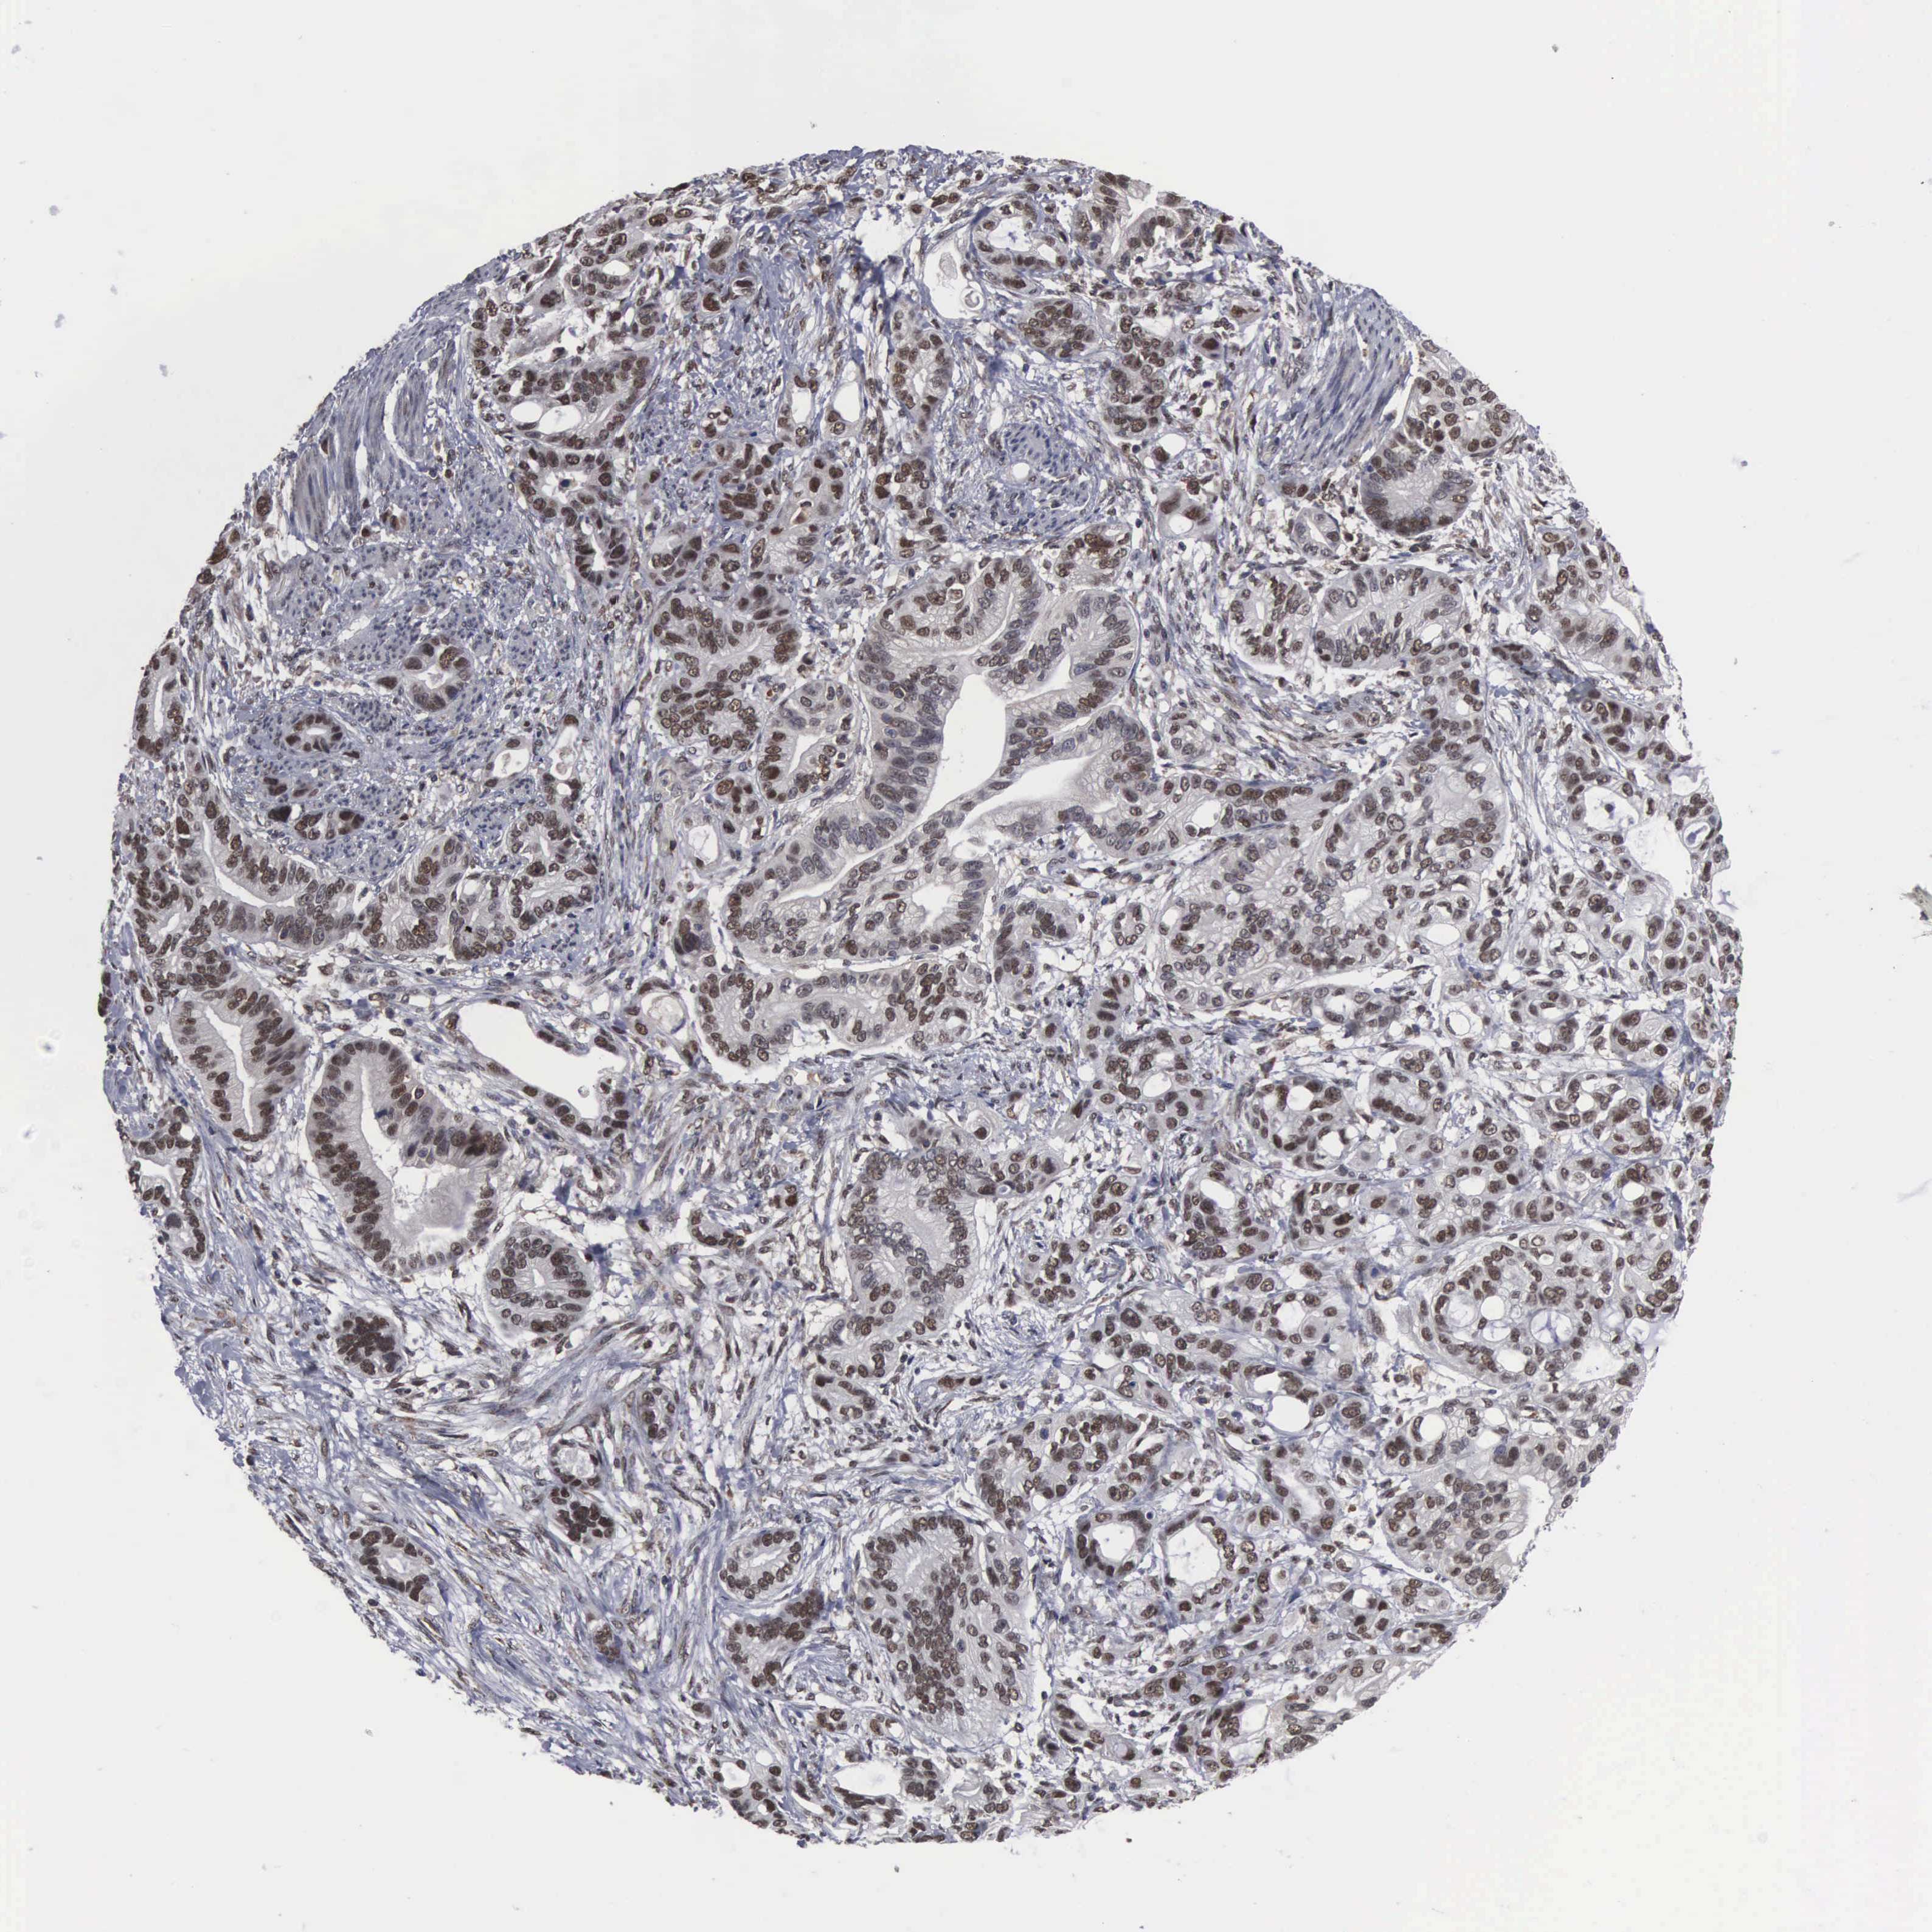

STOMACH CANCER - Protein expressioni

A mouse-over function shows sample information and annotation data. Click on an image to view it in a full screen mode. Samples can be filtered based on level of antibody staining by selecting one or several of the following categories: high, medium, low and not detected. The assay and annotation is described here.

Note that samples used for immunohistochemistry by the Human Protein Atlas do not correspond to samples in the TCGA dataset.

Antibody stainingi

Antibody staining in the annotated cell types in the current human tissue is reported as not detected, low, medium, or high, based on conventional immunohistochemistry profiling in selected tissues. This score is based on the combination of the staining intensity and fraction of stained cells.

Each image is clickable and will lead to virtual microscopy that enables deeper exploration of all samples and also displays staining intensity scores, fraction scores and subcellular localization as well as patient and tissue information for each sample.

Antibody HPA000943

Staining

High

Medium

Low

Not detected

Intensity

Strong

Moderate

Weak

Negative

Quantity

>75%

75%-25%

<25%

None

Location

Nuclear

Cytoplasmic/membranous

Cytoplasmic/membranous,nuclear

Adenocarcinoma, NOS